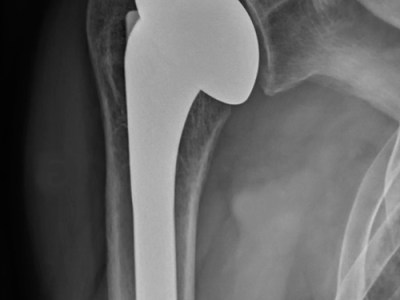

Prothèses totales de hanche : logiciel de planification pré opératoire

Qu’est ce que la planification opératoire ? La planification opératoire est le travail réalisé par le chirurgien en amont de l’implantation d’une prothèse : elle permet au chirurgien de préparer son intervention en anticipant les difficultés potentielles, et en ayant une estimation du positionnement, de la forme et des dimensions des implants à mettre en place. Elle peut se faire « manuellement », en utilisant des calques ou par des logiciels dédiés. L’objectif est de restituer une anatomie au…